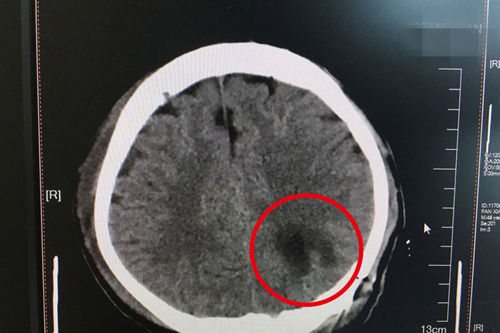

患者术后CT显示:病灶已被完整清除,即右下角深色块状部分